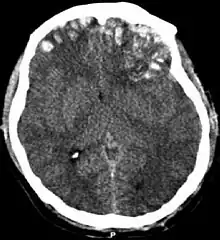

One type of focal injury, cerebral laceration, occurs when the tissue is cut or torn.[37] Such tearing is common in orbitofrontal cortex in particular, because of bony protrusions on the interior skull ridge above the eyes.[31] In a similar injury, cerebral contusion (bruising of brain tissue), blood is mixed among tissue.[23] In contrast, intracranial hemorrhage involves bleeding that is not mixed with tissue.[37]

Hematomas, also focal lesions, are collections of blood in or around the brain that can result from hemorrhage.[11] Intracerebral hemorrhage, with bleeding in the brain tissue itself, is an intra-axial lesion. Extra-axial lesions include epidural hematoma, subdural hematoma, subarachnoid hemorrhage, and intraventricular hemorrhage.[38] Epidural hematoma involves bleeding into the area between the skull and the dura mater, the outermost of the three membranes surrounding the brain.[11] In subdural hematoma, bleeding occurs between the dura and the arachnoid mater.[23] Subarachnoid hemorrhage involves bleeding into the space between the arachnoid membrane and the pia mater.[23] Intraventricular hemorrhage occurs when there is bleeding in the ventricles.[38]